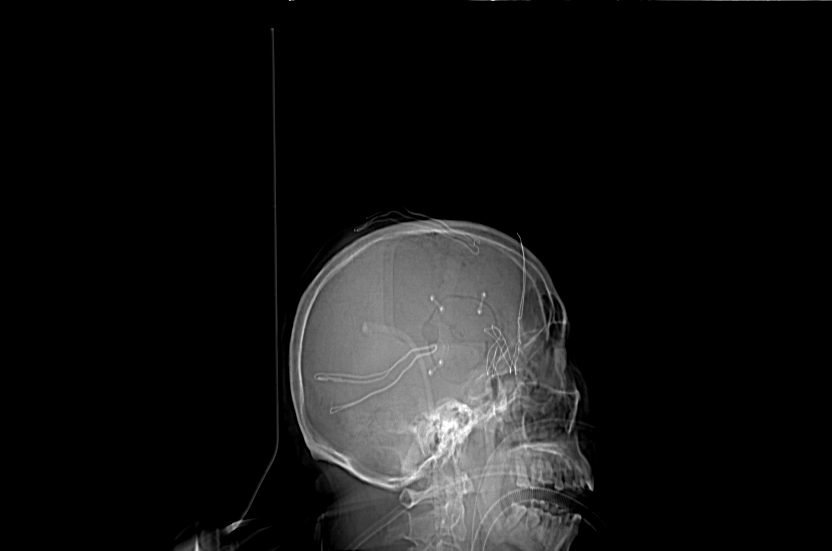

手术方式:翼点入路,小骨窗,经侧裂岛叶入路清除脑内血肿。

术后骨瓣复位